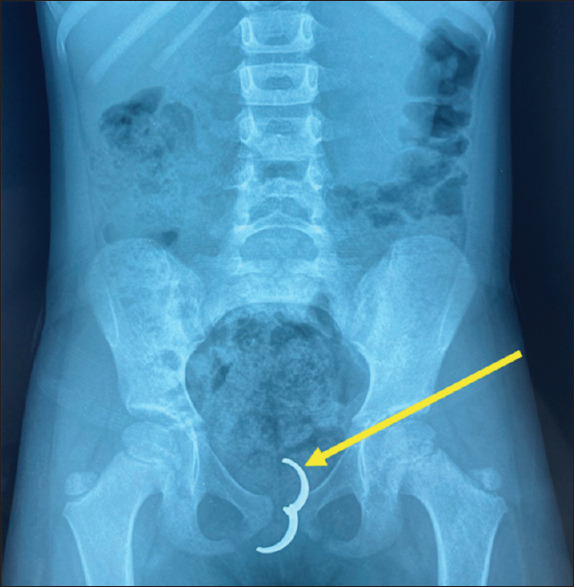

摘要:阴道分泌物是月经前少女常见的妇科疾病。然而,当阴道分泌物持续存在时,必须怀疑阴道内异物(FB)。我们报告了一例转诊的 4 岁女孩,她有 5 个月的持续恶臭阴道分泌物病史。临床检查证实其阴道有脓性分泌物,并伴有阴道肉芽肿。数字直肠检查时,通过直肠前壁摸到一个阴道内的硬物。盆腔 X 光平片显示有一个不透射线的物体,超声波检查证实了该物体在阴道内的位置。患者接受了肉芽肿切除术、FB切除术和抗生素治疗。12 个月的随访结果无异常。

Abstract: Vaginal discharge is a common gynaecologic complaint in pre-menarchal girls. However, an intravaginal foreign body (FB) must be suspected when it is persistent. We report the case of a referred 4-year-old girl with a 5-month history of persistent foul-smelling vaginal discharge. Clinical examination confirmed purulent vaginal discharge, along with a vaginal granuloma. A hard, intravaginal object was felt through the anterior rectal wall on digital rectal examination. A plain pelvic X-ray revealed a radiopaque object whose intravaginal position was confirmed by ultrasonography. The patient underwent granuloma excision plus FB removal and antibiotic treatment. The 12-month follow-up was unremarkable.